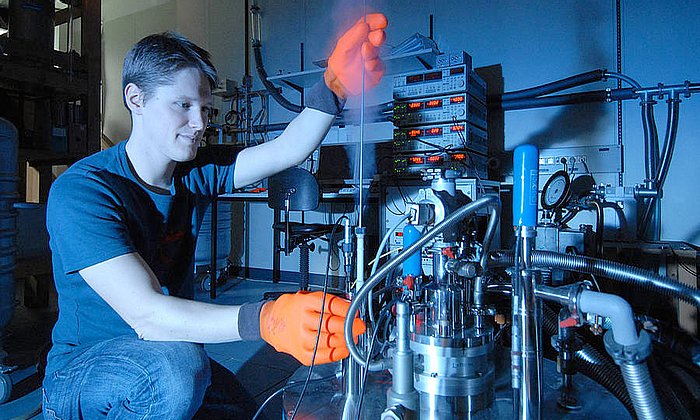

Dem geht nun Josef Lichtinger in seiner Doktorarbeit am Lehrstuhl für Physik der Hadronen und Kerne (E12) der TUM nach. Von der Rechtsmedizin der Ludwig-Maximilians-Universität München (LMU) erhielt er Gewebeproben von Patienten, die mit Lithium behandelt wurden, unbehandelten Patienten und gesunden Vergleichspersonen. Diese setzte der Physiker am Messplatz der Prompten Gamma Aktivierungsanalyse am FRM II einem fokussierten kalten Neutronenstrahl höchster Intensität aus.

Lithium reagiert sehr spezifisch mit Neutronen und zerfällt in ein Helium- sowie ein Tritiumatom. Mit einem speziellen Detektor, den Josef Lichtinger entwickelt hat, können deshalb so geringe Mengen wie 0,45 Nanogramm Lithium pro Gramm Gewebe gemessen werden. „So genau wie mit Neutronen kann man das mit keiner anderen Methode nachweisen“, sagt Jutta Schöpfer, Rechtsmedizinerin an der LMU, die mehrere Forschungsprojekte zur Lithiumverteilung im menschlichen Körper betreut.